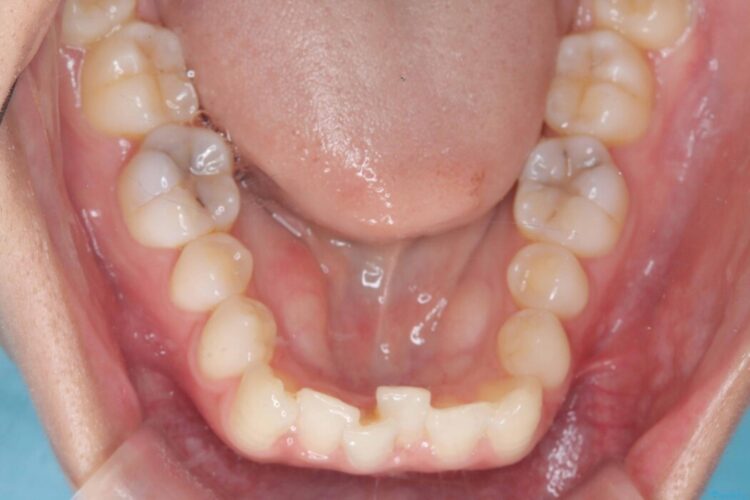

歯のガタつきが気になるとご来院された患者様です。

矯正検査の結果、非抜歯にてワイヤー矯正を行うこととしました。

ガタつきのほかに反対咬合も認められたため、見た目だけでなく嚙み合わせも同時に改善していきます。